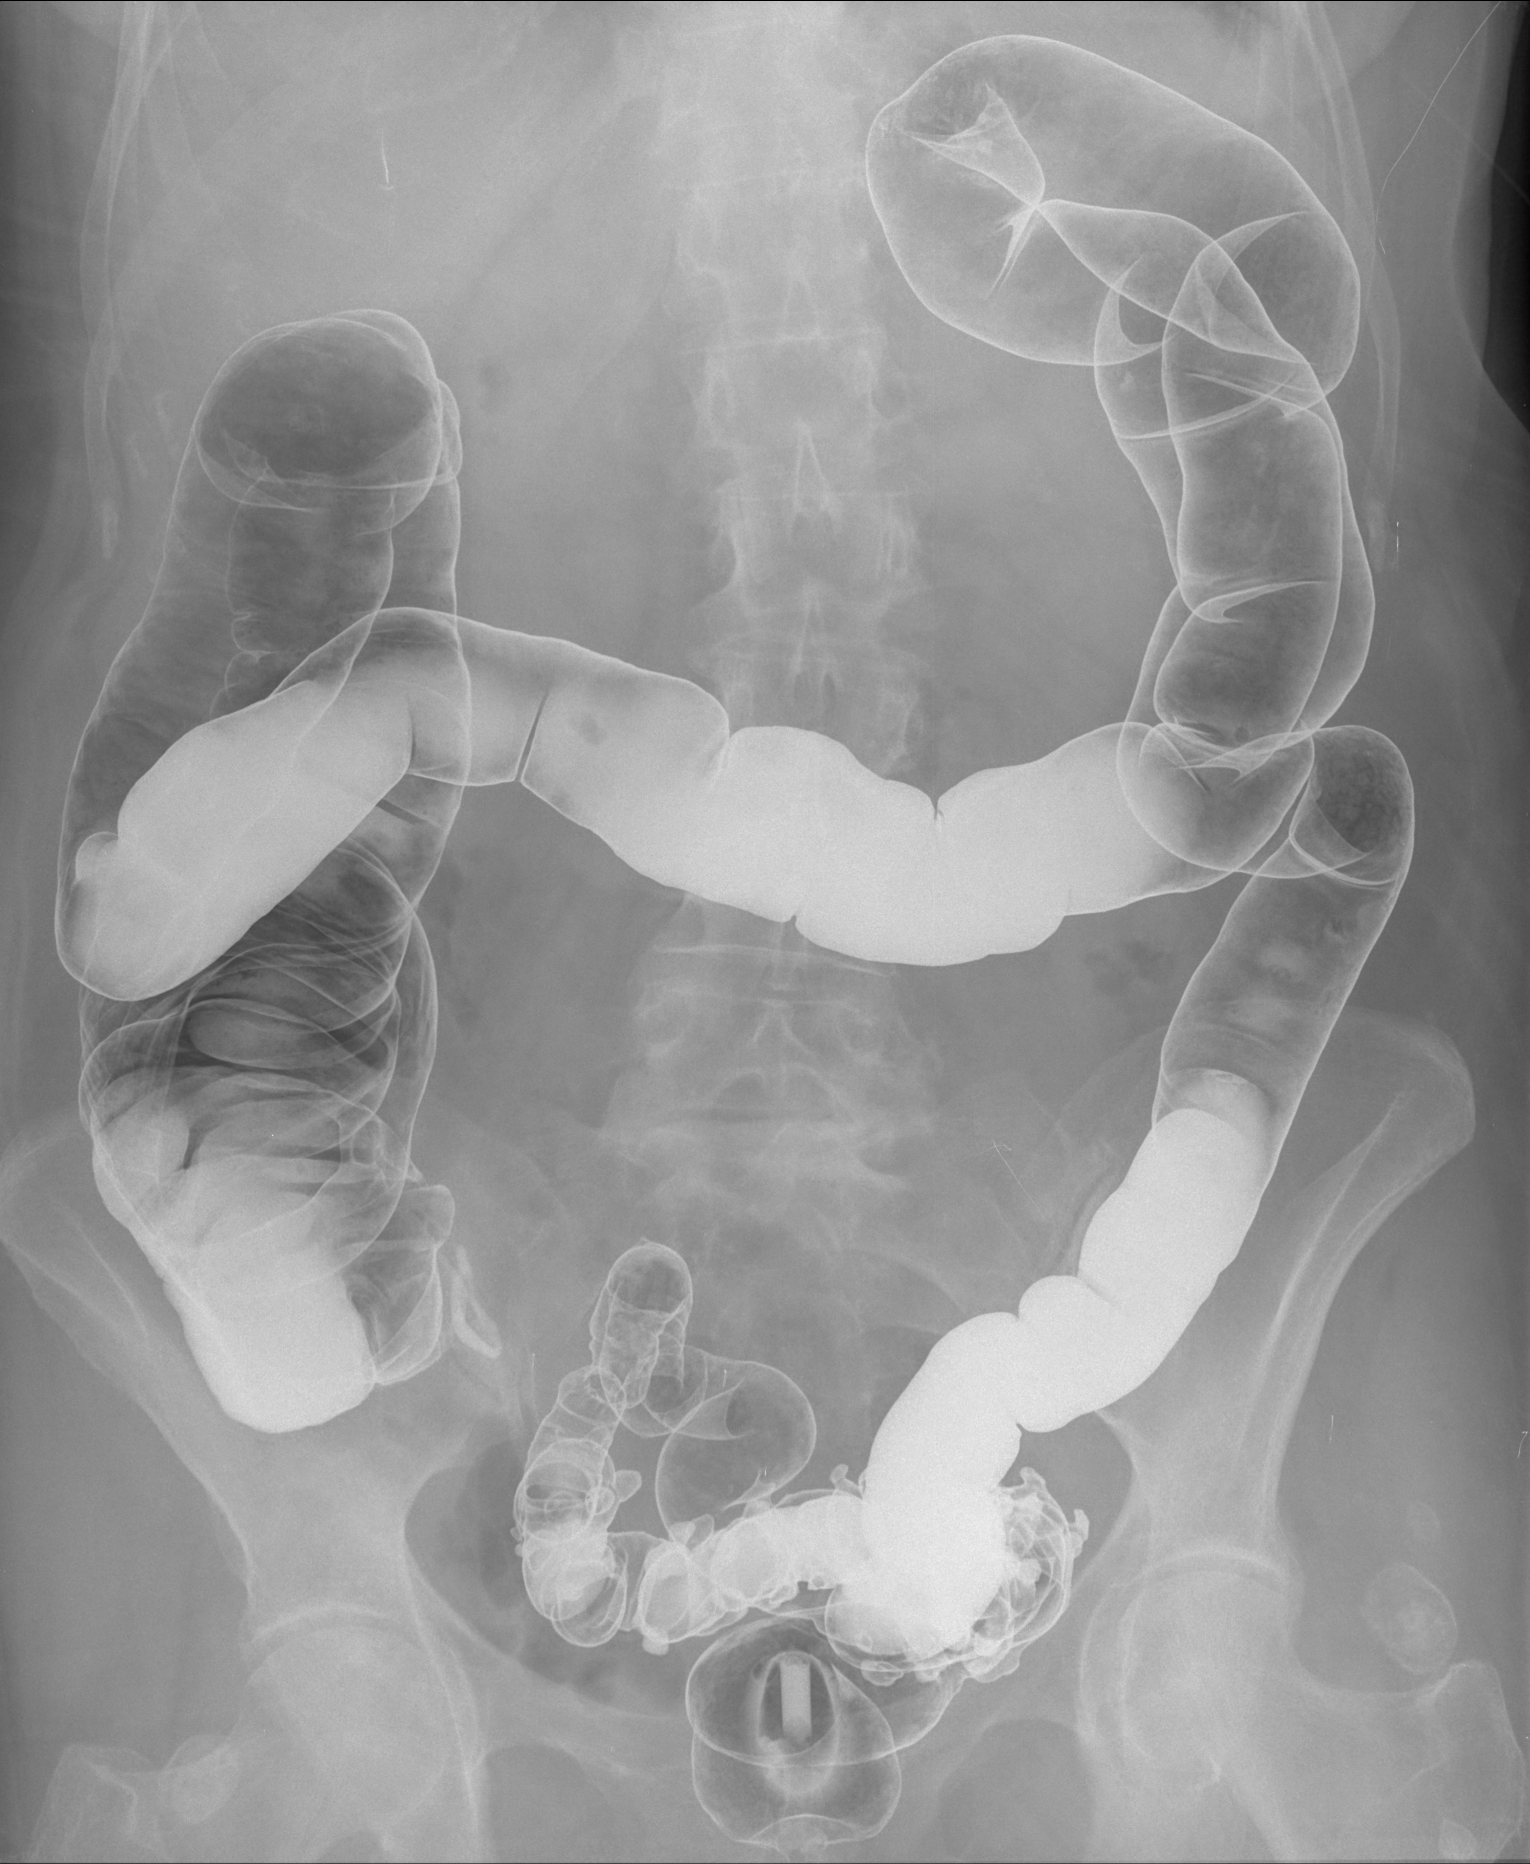

Radiografia dell'addome con mezzo di contrasto (clisma opaco)